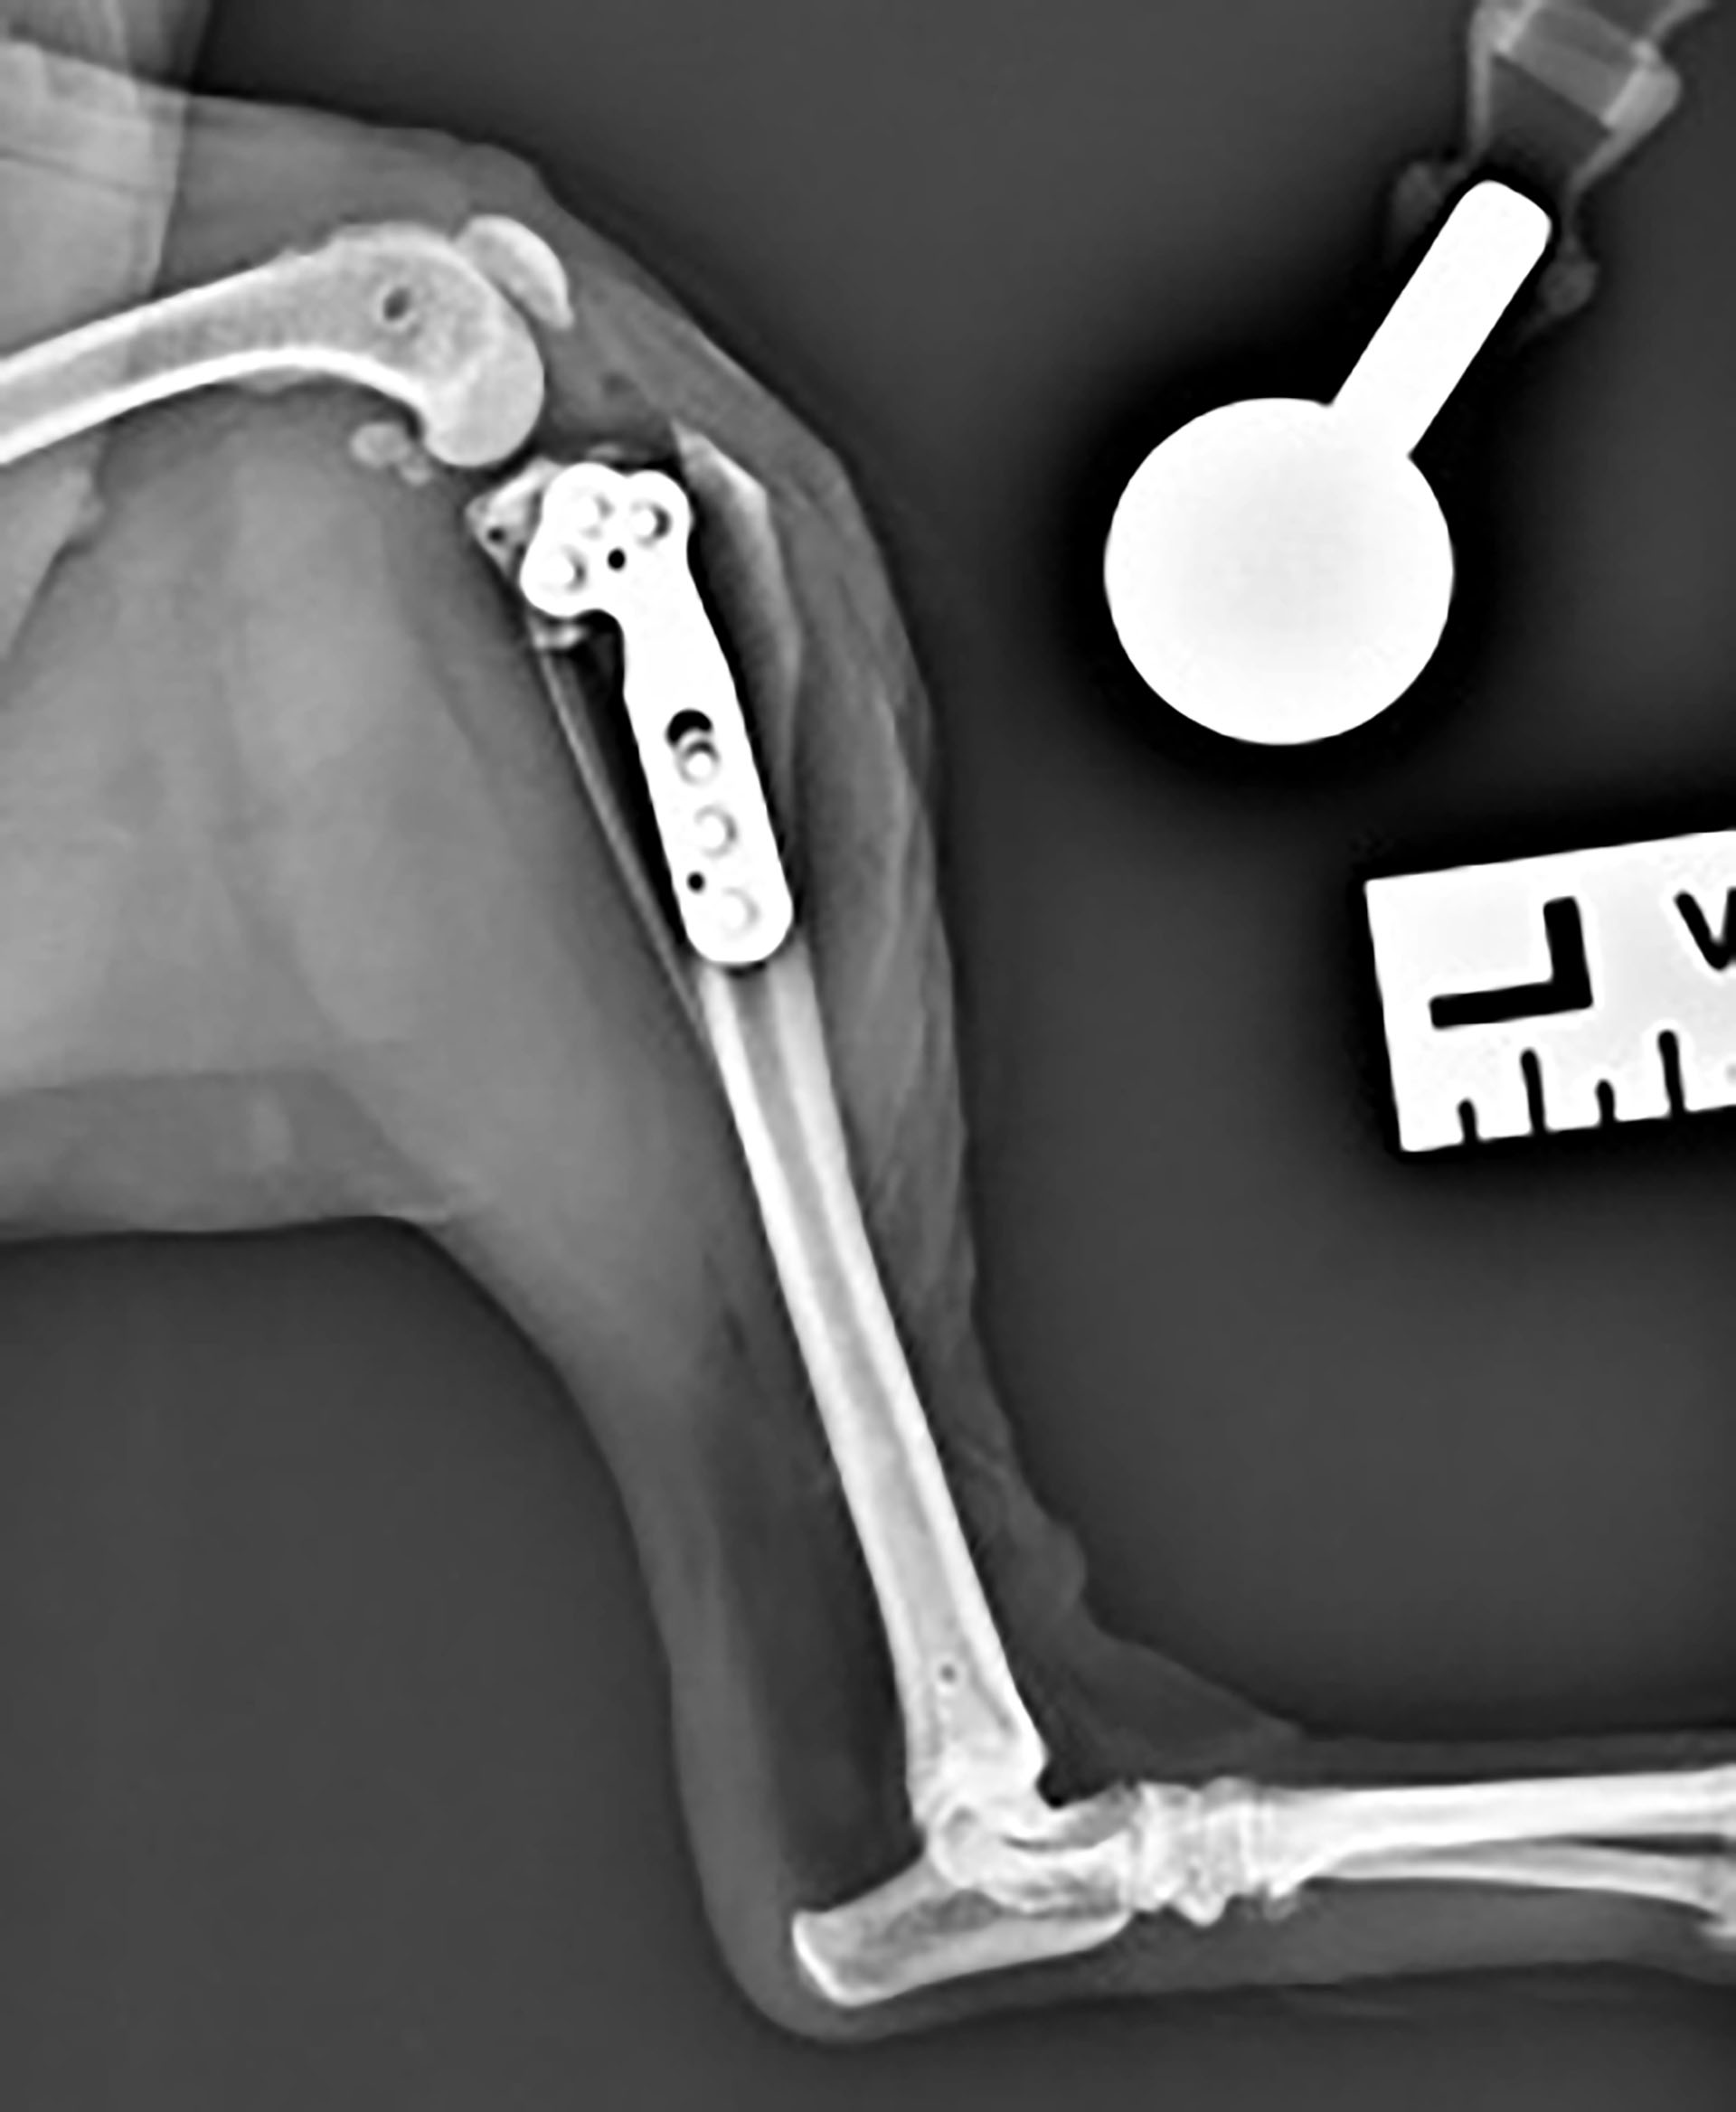

Sevofluranfordamper og ventilator ble skrudd av og pasienten pustet selv. Hunden ble ekstubert ved oppvåkning. Det ble gitt 1 mg/kg maropitant subkutant mot kvalme og 2 mg/kg robenakoksib subkutant mot smerte. Såret ble vasket og det ble lagt på et mepore plaster. Et fentanyl depotplaster 12 µg/time ble påsatt på høyre flanke. Det ble gitt fentanyl CRI etter operasjonen da plasteret ikke hadde effekt før etter 12 timer. Postoperativt ble det utført røntgenbilder av kneleddet (Figur 6 og 7).

Figur 6. Kraniokaudal projeksjon av kneledd postoperativt med plate og skruer.

Figur 7. Laterolateral projeksjon av venstre kne postoperativt.

Røntgenbildene viste tilfredsstillende resultat med TPA på fem grader. Det var tilfredsstillende osteotomiorientering, kompresjon, plateplassering og skruelengder. Hunden ble værende på hospitalet til dagen etter. Hun fikk fentanyl CRI i en rate på 3 µg/kg/time og intravenøs væske i form av ringer acetat 2 ml/kg/time. I løpet av natten ble fentanyl CRI titrert ned til 2 µg/kg/time. Hunden var i god form dagen etter operasjonen, spiste med god appetitt, og hadde en temperatur på 37,6 ˚C. Hun var respiratorisk og sirkulatorisk stabil og reiste hjem til eier denne dagen. Hun tok litt støtte på benet, og godtok å manipulere med det. Huden rundt operasjonssåret hadde mild erytem og mildt ødem. I tillegg til smerteplasteret hun hadde på seg fikk hun også robenakoksib 1 mg/kg (totalt 10 mg) som ble gitt per os en gang daglig i fire uker. 14 mg/kg gabapentin per os to ganger daglig ble gitt som ekstra smertelindring den første uken. Det ble satt opp kontroll med stingfjerning 14 dager etter operasjonen, og røntgenkontroll var planlagt seks uker etter operasjonen. Hunden ble holdt i ro frem til røntgenkontrollen. Fentanylplasteret ble fjernet tre dager senere.